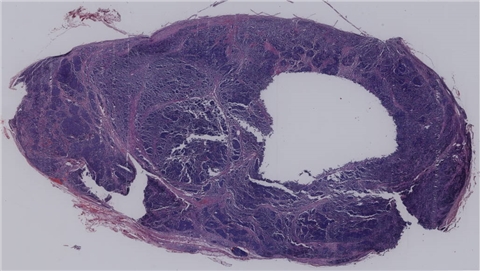

淋巴结转移癌